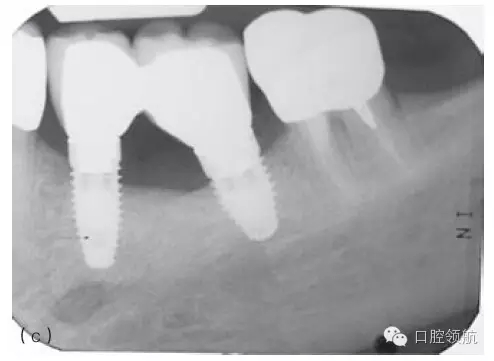

因種植體裝置界面的扭矩可能會(huì)使平臺(tái)連接出現(xiàn)潛在的變形,故應(yīng)注意使該扭矩最小化。Ⅳ類骨植入種植體時(shí)要優(yōu)先在骨上敲打擠壓而不是依靠種植體來擠壓骨洞。許多廠家會(huì)提醒不要超過手術(shù)操作時(shí)推薦的扭矩,以減小折斷的可能性(圖5.3a~c)。

圖5.3 (a)Ⅰ類骨中的種植體內(nèi)連接和界面破損的影像學(xué)表現(xiàn)。(b)取出種植體,發(fā)現(xiàn)沿著種植體平臺(tái)的損壞。(c)在重新放置的種植體上行聯(lián)冠修復(fù)完成2年后的影像學(xué)表現(xiàn)。